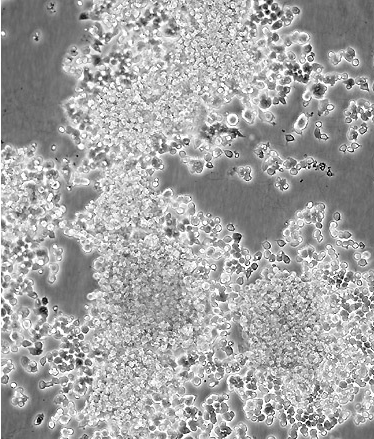

中文名稱 大鼠腎上腺嗜鉻細(xì)胞瘤細(xì)胞(低分化)

細(xì)胞描述 該細(xì)胞系來(lái)自能移植的雄性大鼠腎上腺嗜鉻細(xì)胞瘤。這些細(xì)胞表達(dá)神經(jīng)生長(zhǎng)因子(NGF)受體。NGF可誘導(dǎo)產(chǎn)生神經(jīng)表型。這些細(xì)胞不合成腎上腺素。